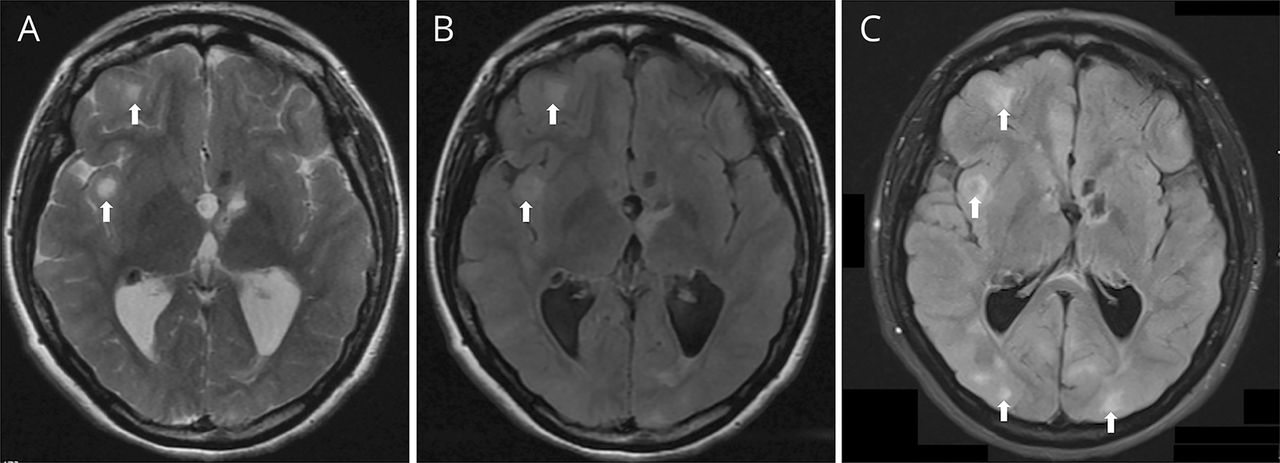

一名22岁妇女与结节性硬化症(TS)和一个不完整的切除左星形细胞瘤提供四年的历史视觉恶化。神经系统检查发现左相对瞳孔传入障碍(RAPD) (视频1),一个苍白的左视神经盘。视力是20/100双边和左优越的视野被损失。光学相干断层扫描显示左视网膜错构瘤(图1)。对比度增强脑部MRI显示双边皮层和皮层下块茎(图2)。Marcus-Gunn学生或RAPD表示视神经病变是一种特异性的功能。1TS眼病包括视网膜和虹膜错构瘤,脉络膜缺损,1例虹膜和睫状体。2